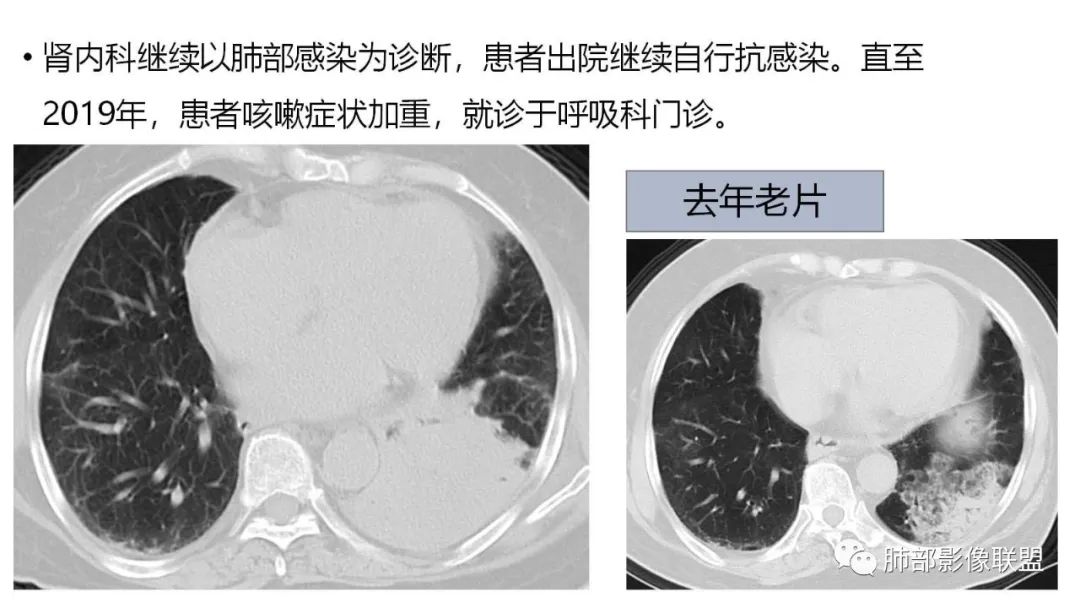

9.粘液腺癌的变化规律:结节缓慢发展而来,向周围播散形成斑片后可快速进展,有时支气管镜后或粘液排出后局部可形成好转的假象。病灶可沿肺泡和支气管播散。

三、本例是一个误诊多年的病例,给我们很多启示:

1.多学科探讨的重要性:肾内科忽视肺部病变,后续需要呼吸、影像、病理共同探讨。

2.粘液腺癌易伪装成肺炎的形态,尤其是当患者本身具有免疫色彩的时候,易误诊为间质性肺炎,或肺部感染。若治疗无效,取得病理很重要。

3.粘液腺癌常常因为标本不够,病理无法诊断,影像诊断很重要,取病理方案很重要。甚至多次取病理。

4.回到本例,左下肺病变两次好转,均未经过肿瘤治疗,第一次是支气管镜后,第二次是当其他病变都在进展的情况下,左下肺病变范围反而缩小趋于浅淡。